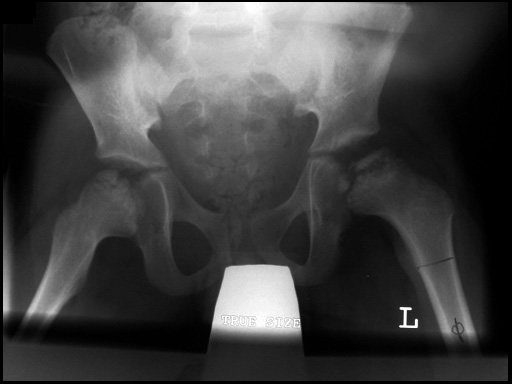

6-year-old boy with Legg-Calv-Perthes disease, preoperative x-ray.